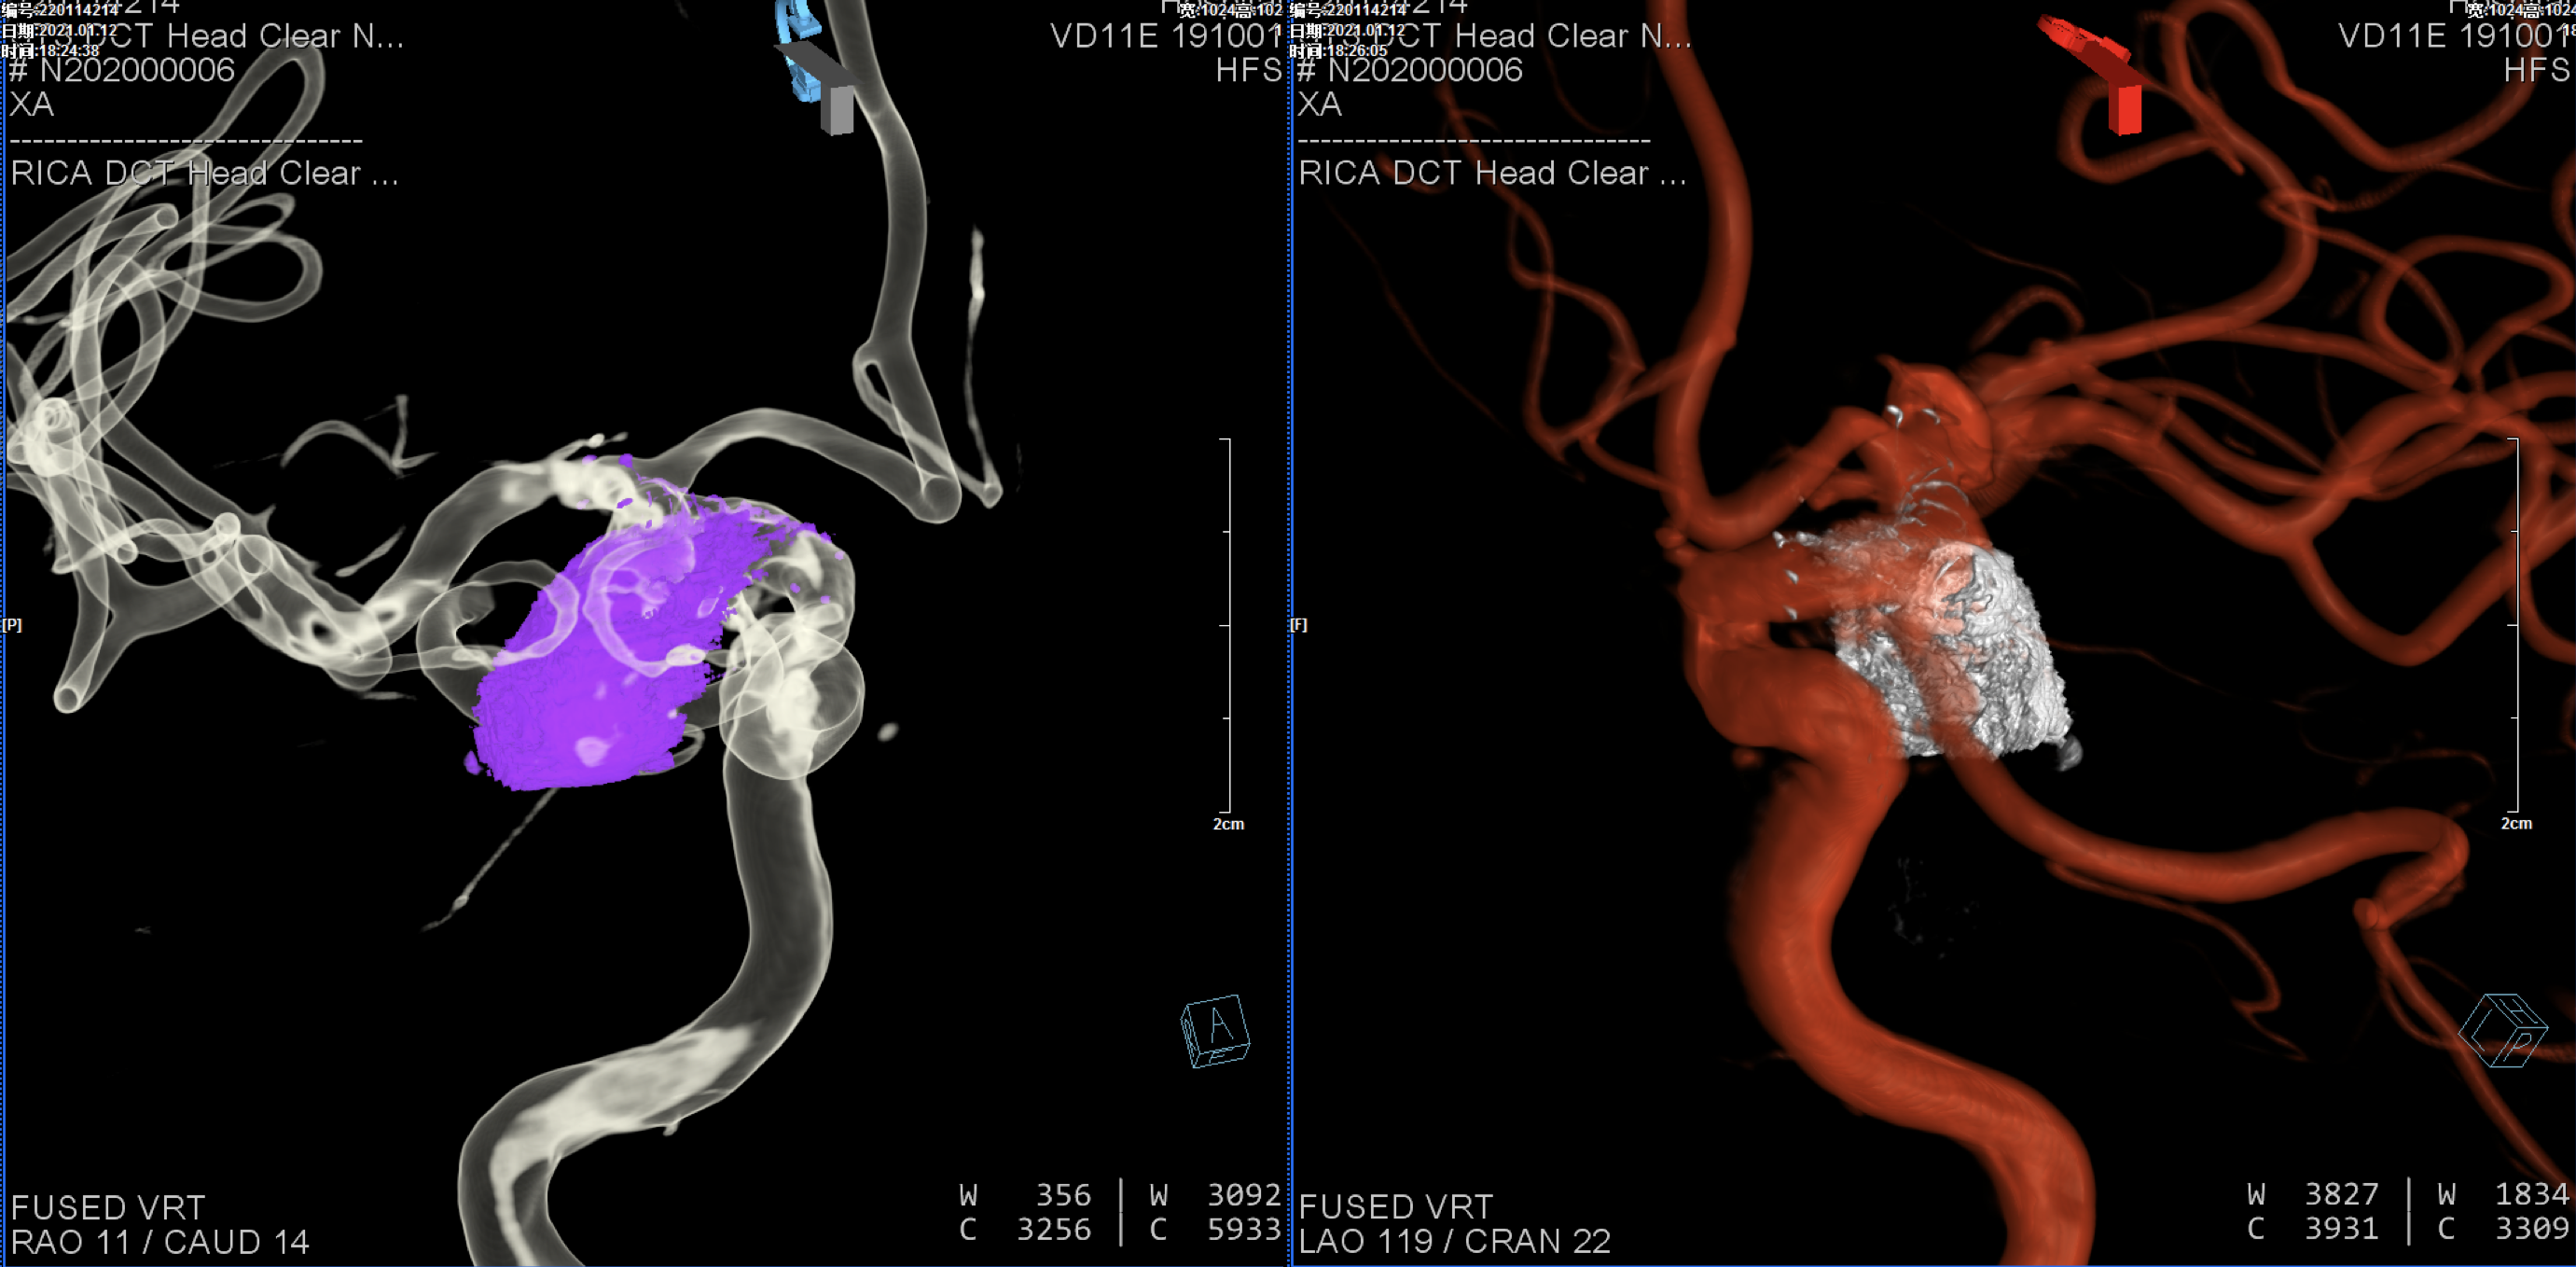

入院后完善头颅CTA:右侧颈内动脉后交通动脉瘤。

后交通动脉瘤大小约22mm*12mm。

右颈内动脉三维重建:粗大的后交通动脉自近心端瘤颈发出!闭塞后交通动脉可能会出现临床症状,似乎可以通过支架的推“灯笼”保护,但瘤体较大,尽可能栓塞完全,故考虑瘤腔内双微导管分区填塞!